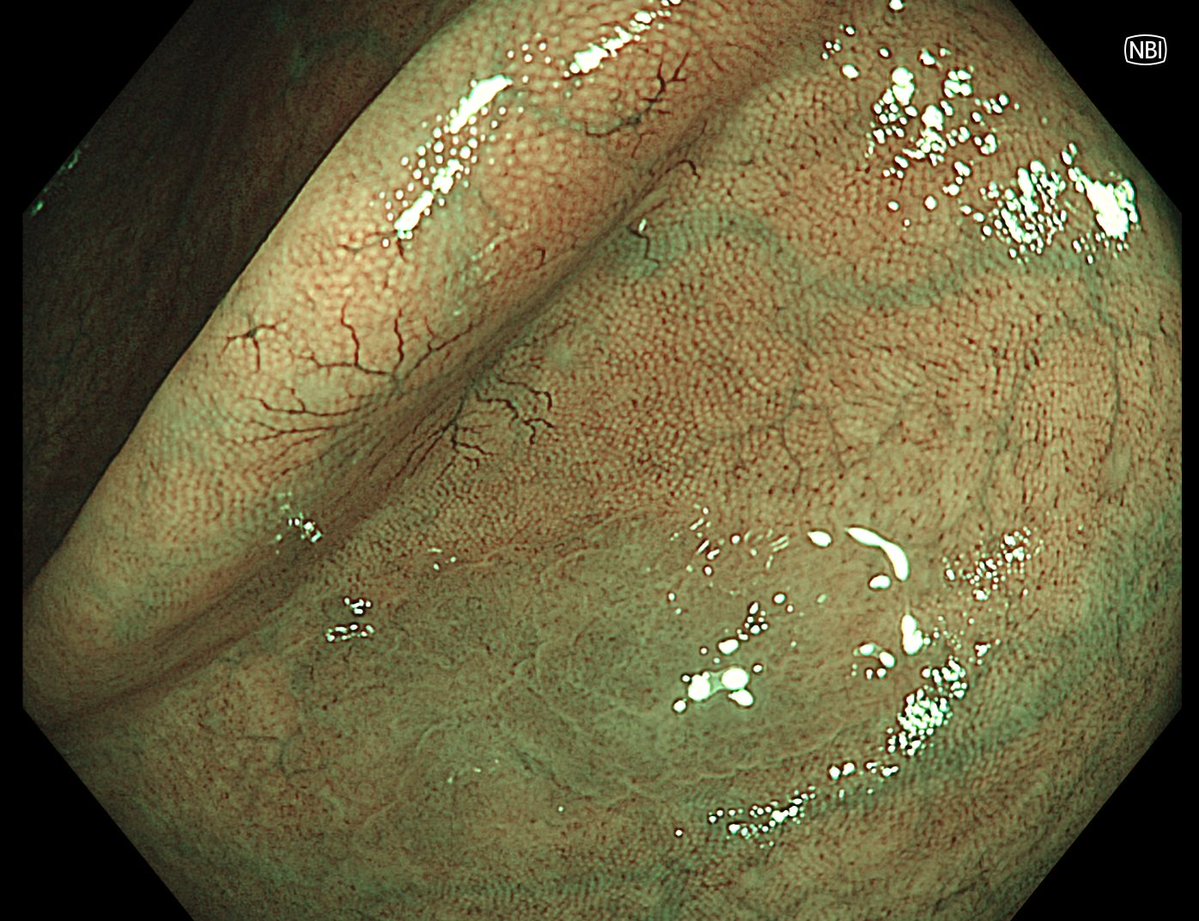

This lesion was diagnosed in the distal sigmoid colon? What do you do next?